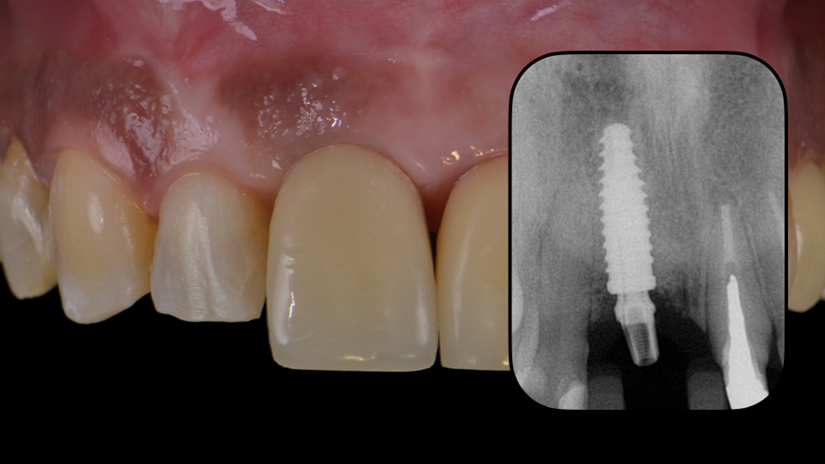

O caso foi conduzido com planejamento cuidadoso, moldagens analógicas e provas clínicas. A reabilitação foi finalizada com a instalação de uma coroa metalocerâmica parafusada, garantindo estética, funcionalidade e reversibilidade do conjunto protético.

Esse protocolo evidencia como a seleção correta do pilar protético, respeitando angulação e diâmetro adequados, pode contornar limitações anatômicas e transformar um caso potencialmente desfavorável em um resultado previsível e satisfatório.